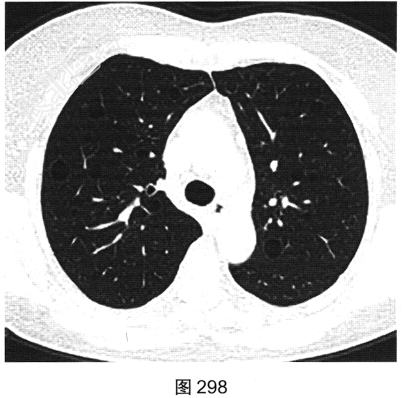

- 多项选择题3.[提示]HRCT图像如图298~图301所示。从患者的HRCT图像中可见哪些阳性征象( )

A、双侧腋窝及纵隔内多发增大淋巴结

B、双肺多发薄壁透亮影

C、小叶间隔增厚

D、右肺多发钙化结节灶

E、双肺多发磨玻璃样密度影

F、支气管扩张

- 多项选择题4.[提示]患者免疫筛查:ANA、RA及干燥综合征相关抗体谱、ACE(一)。根据患者免疫筛查结果, 结合其临床表现和CT影像特征,应优先考虑的诊断是( )

A、肺朗格罕细胞组织细胞增生症

B、支气管扩张

C、淋巴细胞性间质性肺炎

D、肺淋巴管平滑肌瘤病

E、特发性肺间质纤维化

F、肺气肿